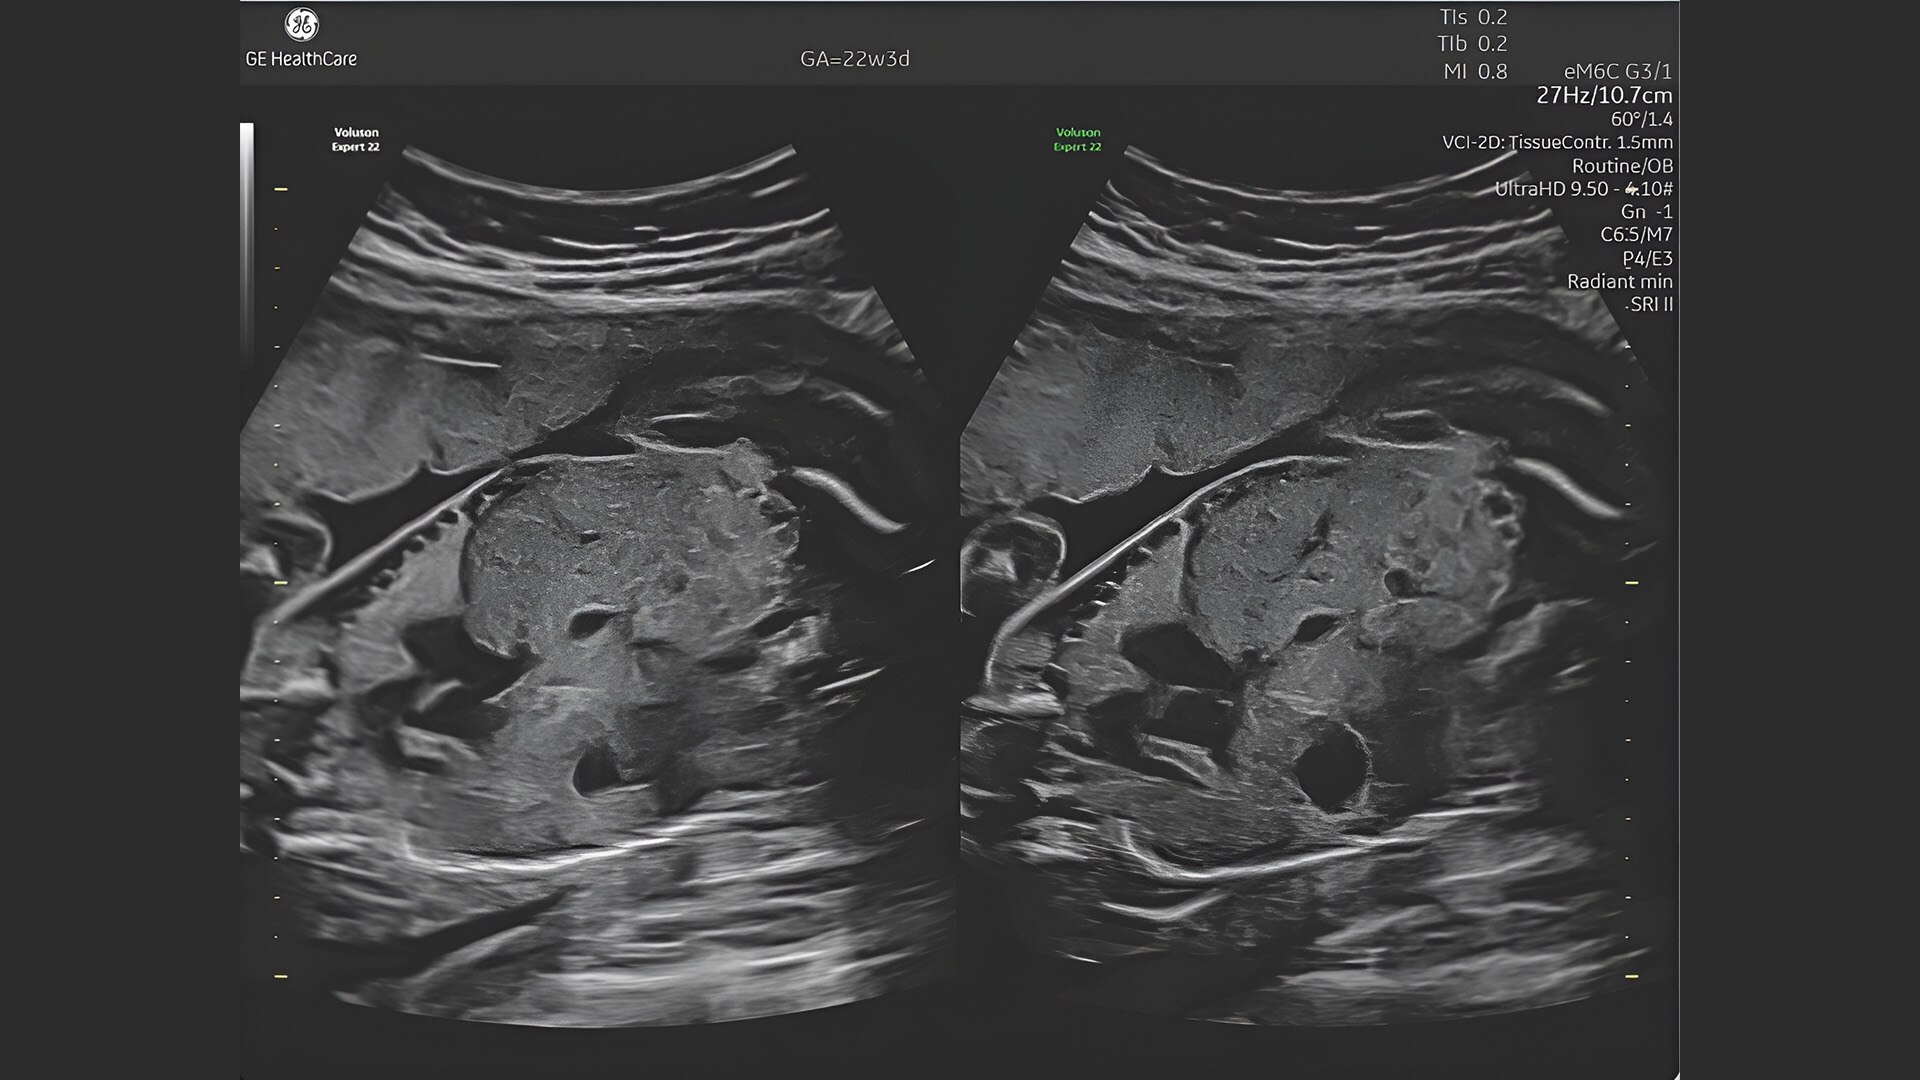

First trimester exams

Perform detailed exams with high-resolution for early insights to fetal health

Complex cases come with enough uncertainty. That's why the Voluson Expert 22 is specifically designed for in-depth assessment of complicated anatomy — with pioneering first trimester, fetal cardiac, gynecological, and other pivotal technologies that focus on early detection and intervention.